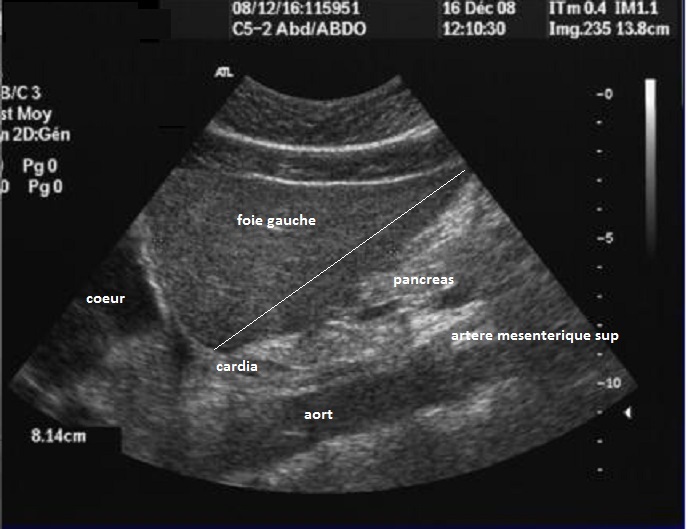

Echographie en

Doppler , methode trés utilise pour les

pathologies hepatiques , par cette methode on peut

differencie et verifie le flux monophasique et

triphasique de la veine porte et veine sús

hepatique . Par encoder de vitesse du flux sanguine

des vaiseaux intra hepatique on peut codee en

couleur le trajet des artere et veines

intrahepatique , ce qui permetre de diferencie la

richesse de vascularisation d"un tumeur ou une

lesion intrahepatique ( maligne ou begnin ) . |